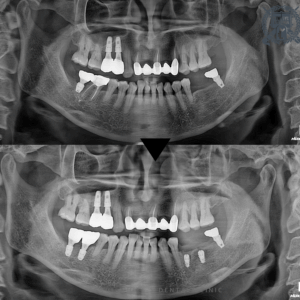

영도치과, 골이식을 통한 상악 임플란트 시술 사례

영도치과, 골이식을 통한 상악 임플란트 시술 사례 여러 치과 치료 가운데 많은 분들이 선택하는 시술이 바로 임플란트입니다. 그런데 상담 과정에서 “치조골이 충분하지 않아 식립이 어렵다”는 이야기를 들어본 분들도…